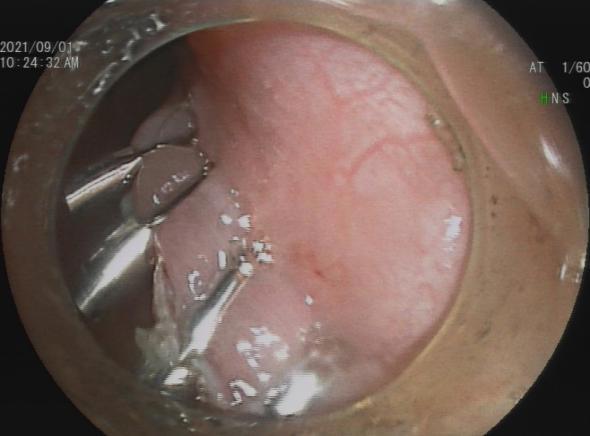

3.早期消化道肿瘤ESD技术

内镜下粘膜剥离术(ESD),具有超级微创、安全性高、住院时间短及费用低等优势,治疗早期胃癌、食管癌、大肠癌等病变,5年生存率超90%。

直肠巨大绒毛状腺瘤 内镜下粘膜剥离过程

粘膜剥离术后创面 剥离的巨大腺瘤